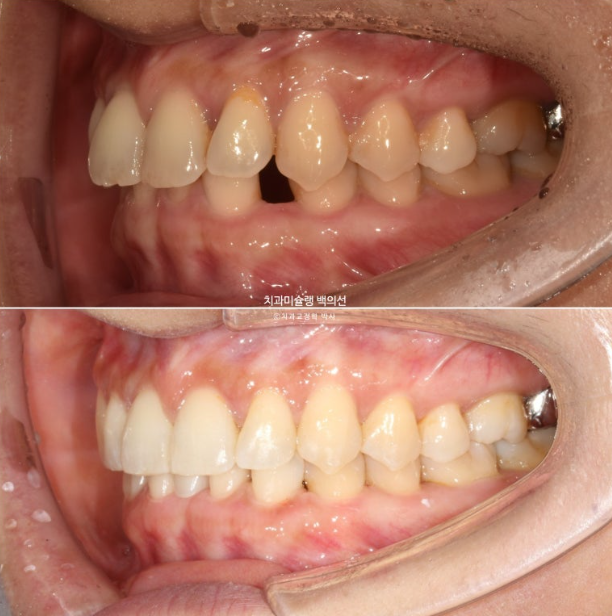

교정치료를 위해 내원한 환자분입니다. 아래 앞니 두 개가 없어서 이 사이 벌어짐을 치료하고자 오셨습니다.

윗니가 아랫니를 깊게 덮는 과개교합도 보입니다.

사진에 보이는 구멍은 앞니가 없어 송곳니가 앞니 자리로 이동하고 송곳니와 작은어금니 사이 공간이 벌어져 있습니다.

송곳니가 없는 것 처럼 보이지만 사실은 앞니 2개가 선천적으로 없는 상태입니다.

환자분이 모르고 있던 또 다른 문제는 파란화살표 제 2대구치가 혀쪽으로 쓰러져 있는 것 입니다.